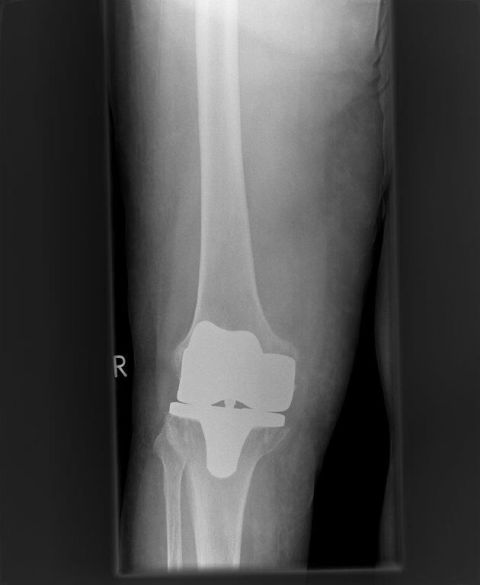

Interimsplatzahlter bei mehrfachem septischem Wechsel mit antibiotikahaltigem Zement

Künstliches Gelenk nach Wiedereinbau gekoppelt